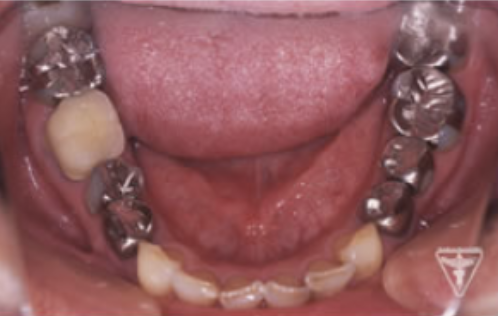

治療前

初診時の正面観・側方観・かみ合わせの面の状態を示します。

下の顎のずれがあるのを確認して下さい。